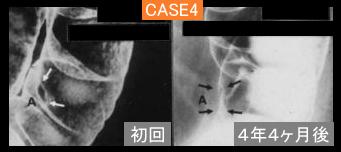

Four cases of type 2 advanced colorectal cancer in which more then three times barium enema were retrospectively studied due to various reasons.

[Image-ID:11843]

Tumor Epitelial Maligno/Adenocarcinoma

parte(separada por órganos)

colon/descendente

método de exámen

Rayos X